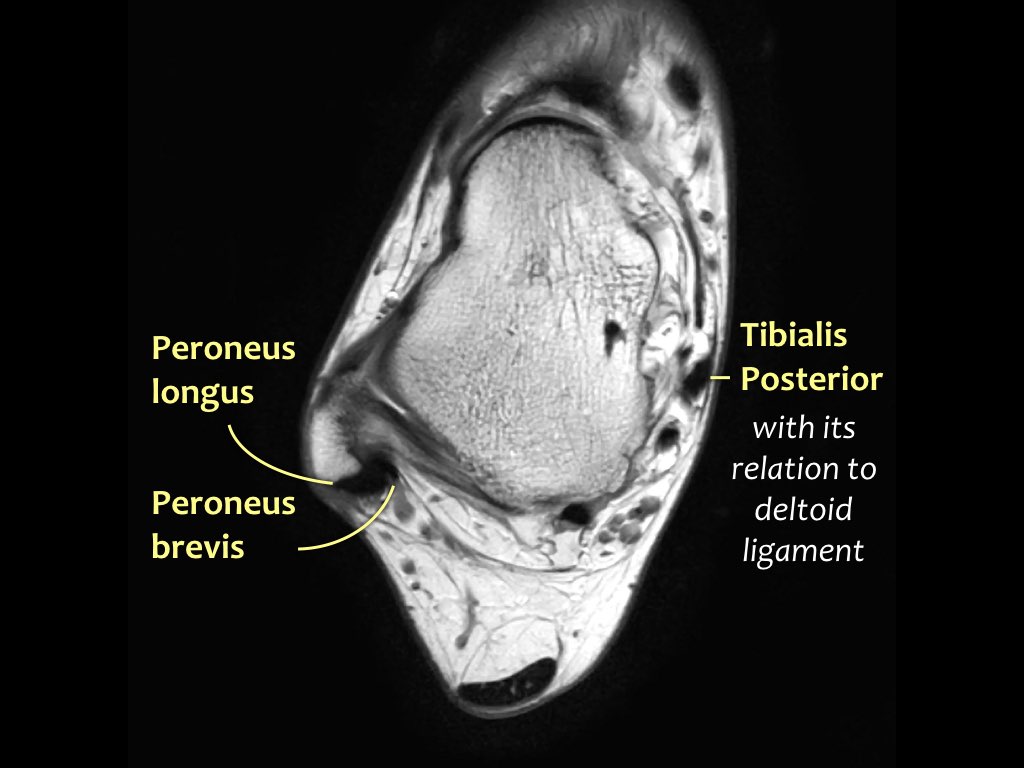

Giải phẫu trên mặt phẳng cắt ngang

Các gân có thể được chia thành bốn khoang:

- Khoang trong (từ trong ra ngoài: Tom-Dick-Harry)

- Gân cơ chày sau (Tibialis Posterior – PTT)

- Gân cơ gấp các ngón chân dài (Flexor Digitorum)

- Gân cơ gấp ngón cái dài (Flexor Hallucis Longus)

- Khoang sau

- Gân Achilles

- Gân cơ gan chân (Plantaris)

- Khoang ngoài

- Gân cơ mác dài (Peroneus Longus)

- Gân cơ mác ngắn (Peroneus Brevis)

- Khoang trước (từ trong ra ngoài: Tom-Hates-Dick)

- Gân cơ chày trước (Tibialis Anterior)

- Gân cơ duỗi ngón cái dài (Extensor Hallucis Longus)

- Gân cơ duỗi các ngón chân dài (Extensor Digitorum)